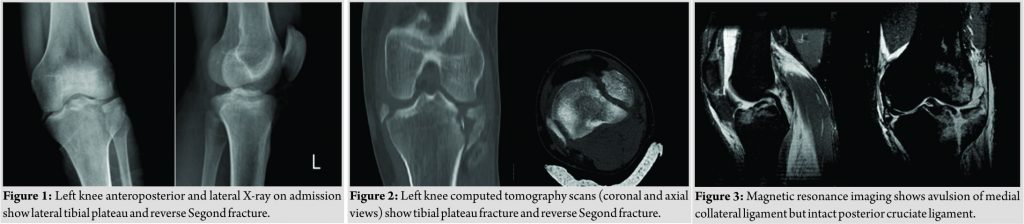

A 24-year-old male was brought to the emergency room after suffering a motorcycle versus car accident. On the initial examination and radiographic evaluation, he had left tibial plateau and reverse Segond fracture (Fig. 1). He had normal vascular and neurologic examination at initial and following evaluations. Computed tomography (CT) scan showed a large fragment avulsed from peripheral rim of medial tibial plateau in addition to lateral tibial plateau fractures (Fig. 2). Magnetic resonance imaging (MRI) showed MCL avulsion, medial meniscus entrapment and ACL tear but intact PCL (Fig. 3). The patient was approached with two separate incisions, and both fractures were fixed (Fig. 4)The medial meniscus was pulled out from fracture site and repaired. No treatment was done for ACL in acute phase. He had full knee range of motion and complete union of fractures after 12 weeks.